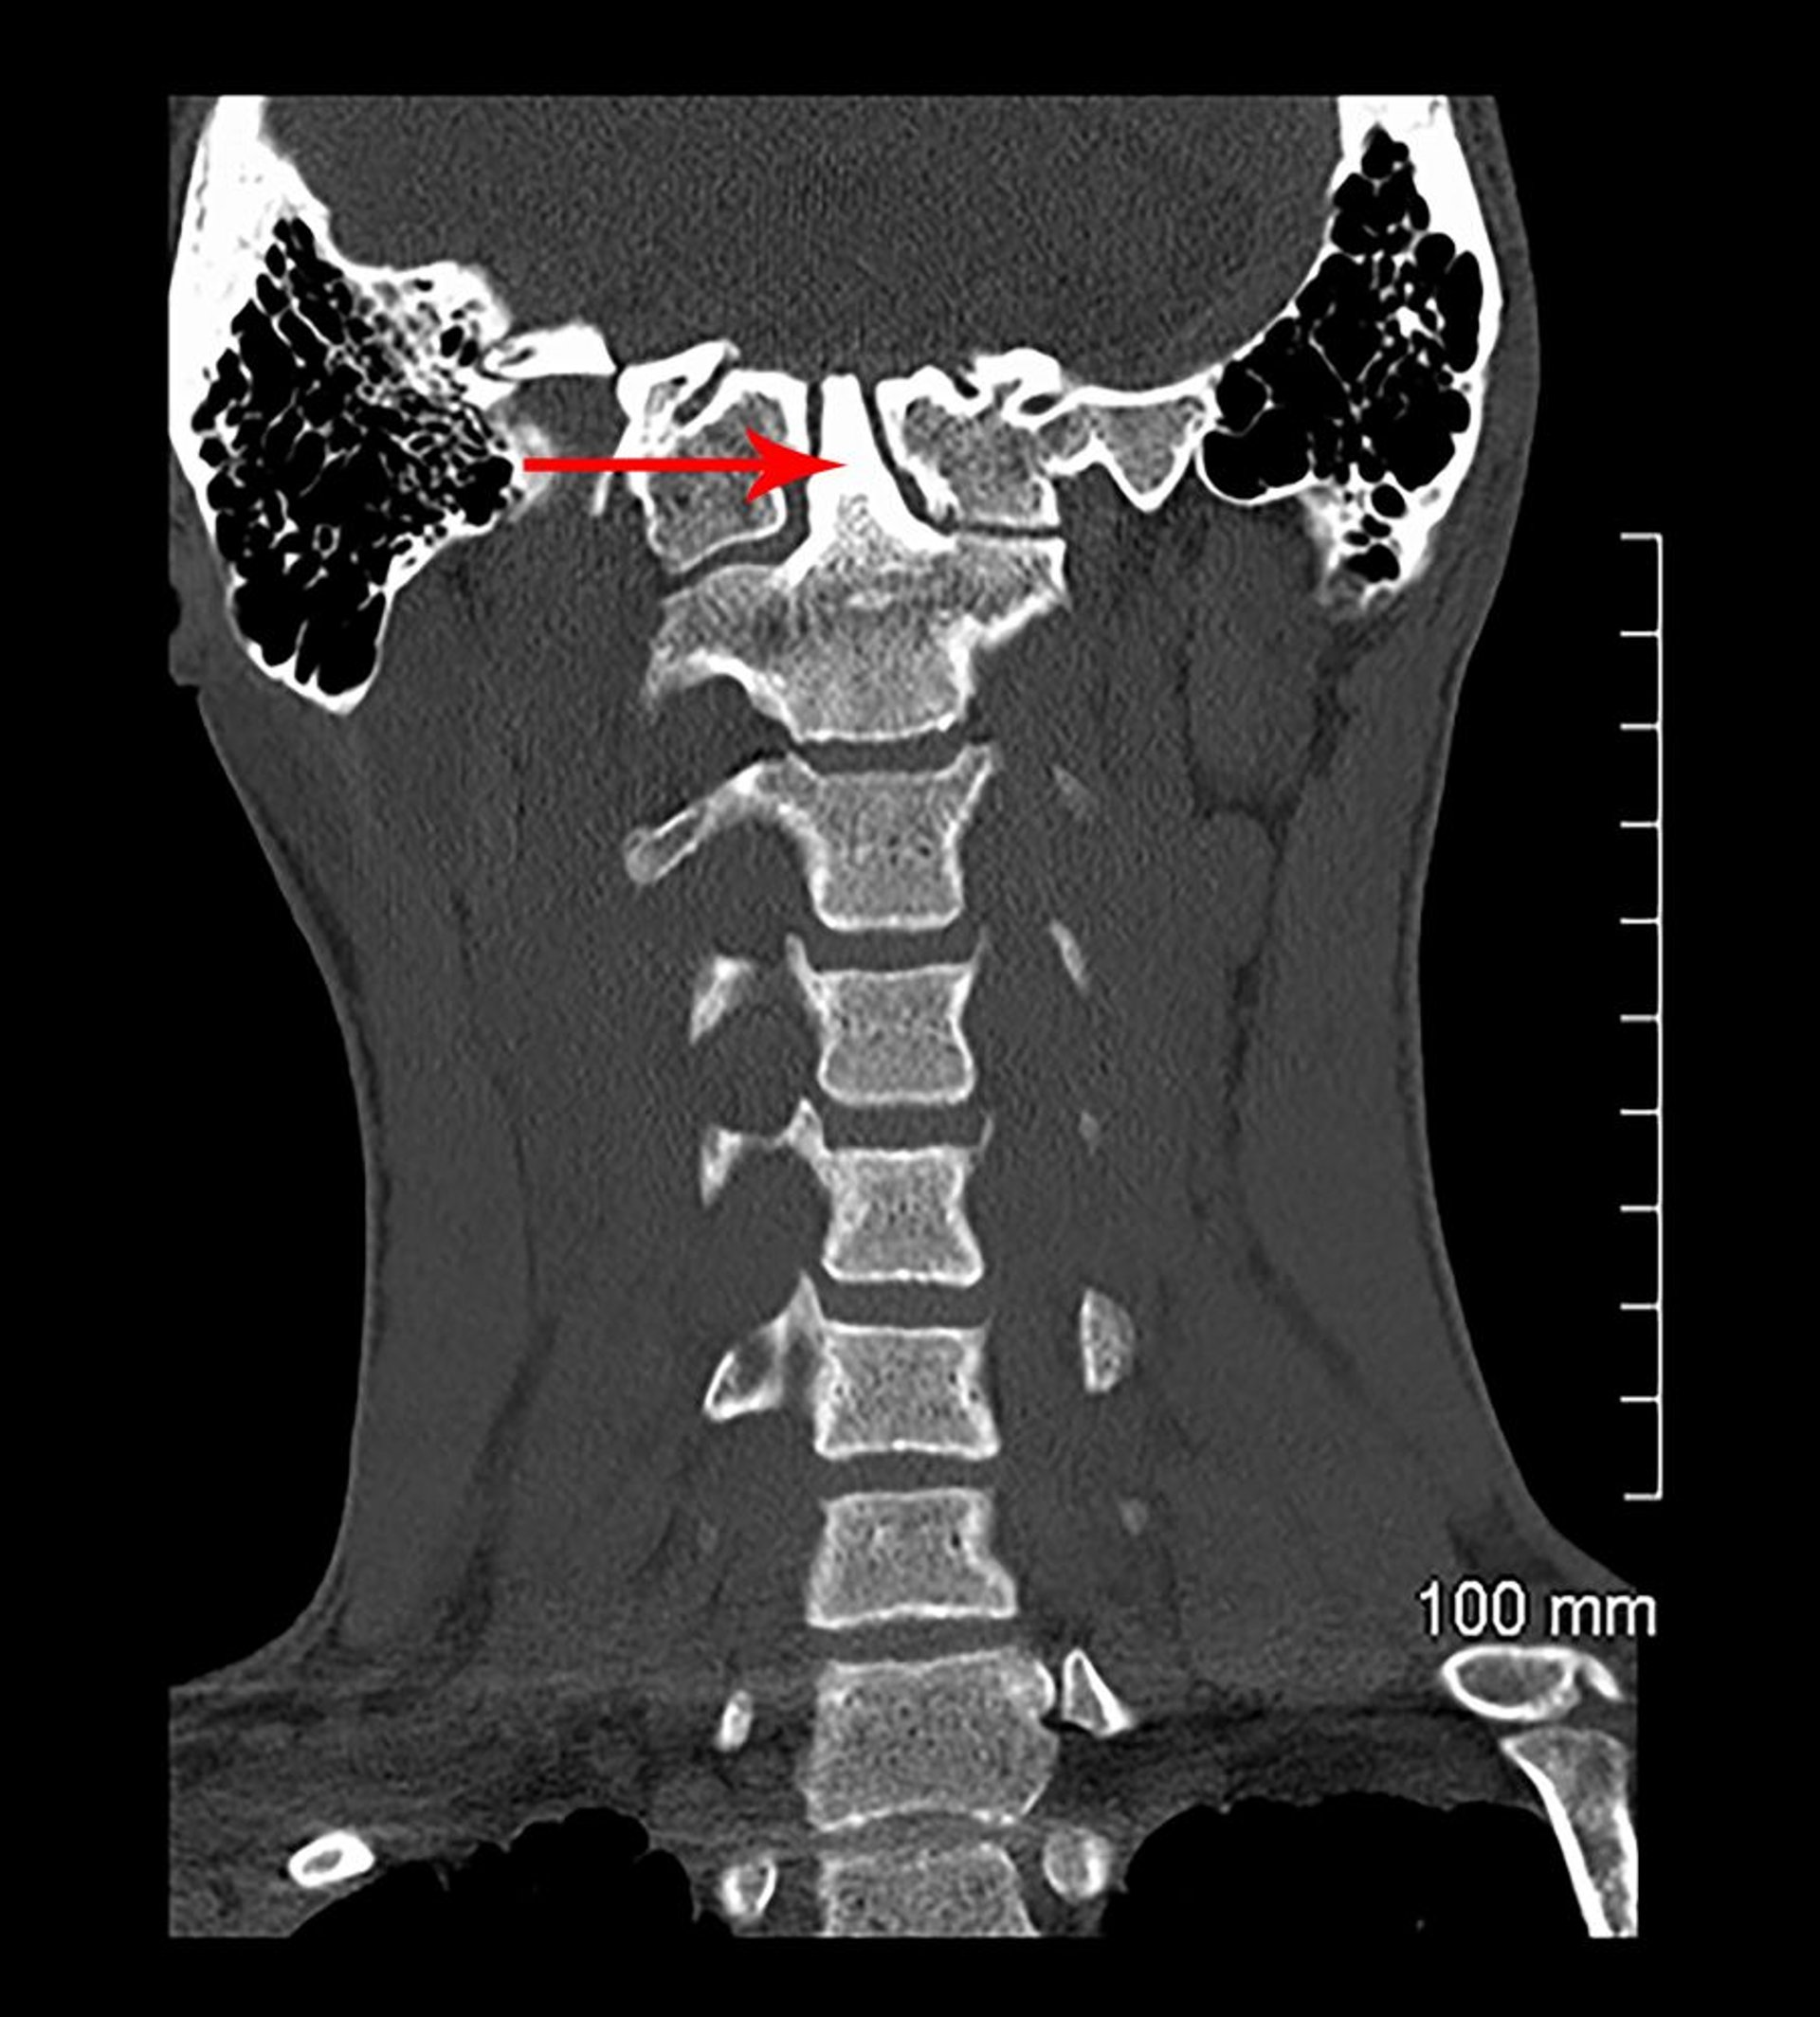

Basiläre Invagination und kongenitale Assimilation (CT)

In dieser koronalen Ansicht einer CT-Aufnahme ist C1 mit der Schädelbasis verschmolzen (kongenital). Der Odontoidfortsatz (durch Pfeil gekennzeichnet) ragt in die Schädelbasis hinein (basiläre Invagination).